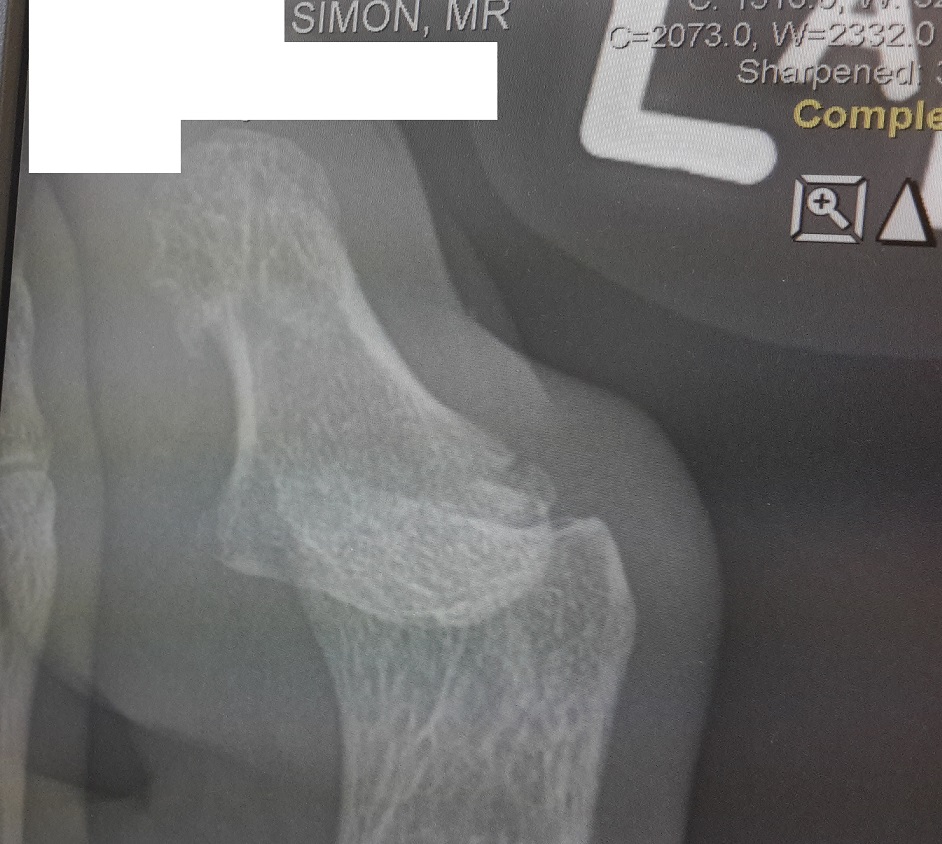

Broken Toe SmallApparently, 100km in ten days is quite a lot on a broken toe. Oops. Oh well.

Thanks to a Fawlty Towers-like hotel in Cornwall and a particularly well-executed kick into a sharp step, I have a tiny fracture on my big toe. D’oh.